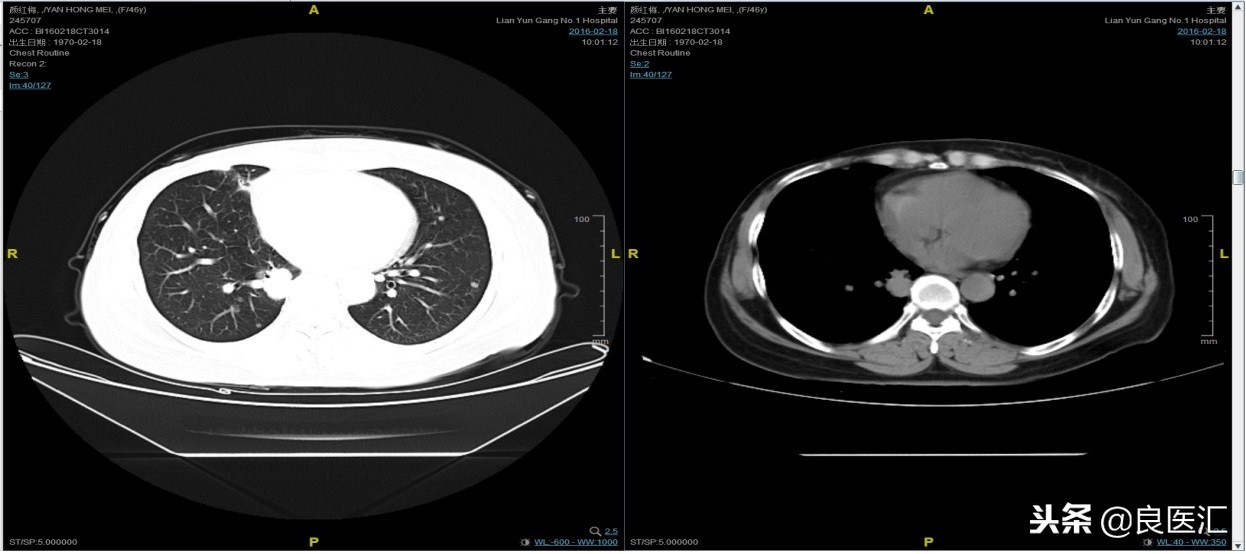

从2016-2-19开始给予紫杉醇+曲妥珠单抗治疗,紫杉醇240mg,3周重复,曲妥珠单抗330mg三周重复。患者末次应用曲妥珠单抗和紫杉醇时间为2016-6-24,紫杉醇共应用4周期。

期间2016-4-22复查CT如下:

2016-7-5化疗结束后复查CT,疗效评价稳定。